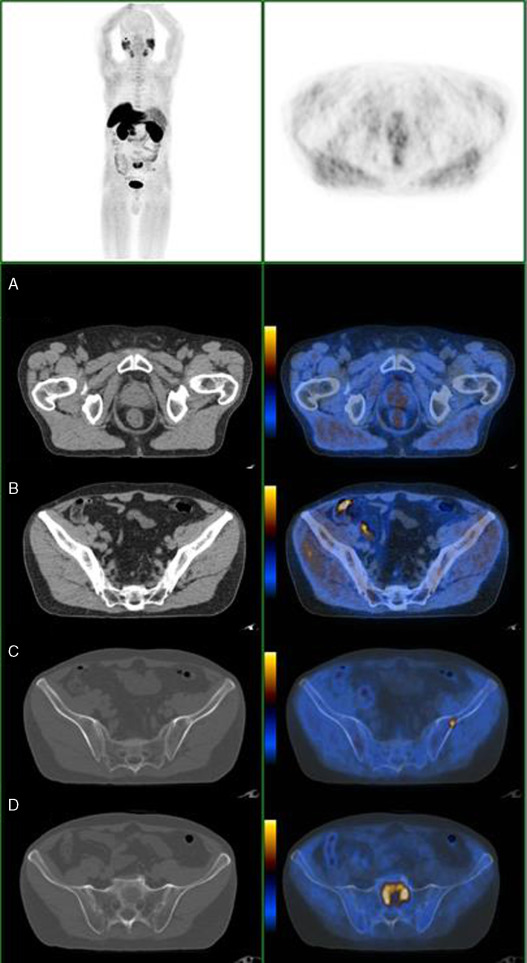

Nas Figura 1 , Figura 2 , Figura 3  ;  Figura 4 apresentam‐se 4 exames PET/CT com FCH‐F18 realizados em contexto de estadiamento inicial de CaP. Na figura 1 encontra‐se um doente apenas com doença prostática com PSA de estadiamento de 48 ng/mL. Na figura 2 apresenta‐se um doente com doença prostática e metastização ganglionar pélvica com PSA de estadiamento de 40 ng/mL. Na figura 3 , o doente apresentava doença prostática e metastização ganglionar à distância e tinha um PSA de estadiamento de 43 ng/mL. Na figura 4 o doente apresenta doença prostática e metastização óssea, e tinha uma PSA de 11 ng/mL.

Doente com CaP com PSA de 11ng/mL, com doença prostática (A), metástase ...

Figura 4.

Doente com CaP com PSA de 11 ng/mL, com doença prostática (A), metástase ganglionar pré‐sagrada com 4 mm (B) e metástases ósseas, no ilíaco esquerdo (C) e em S1 (D).